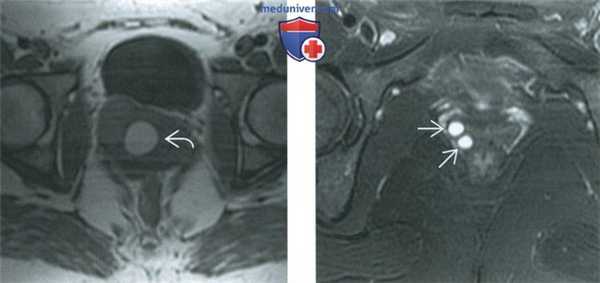

(Слева) При МРТ на Т1-ВИ в аксиальной плоскости у той же пациентки визуализируется гомогенная гиперинтенсивная киста гартнерова канала. Эта картина также свидетельствует об осложнении кисты кровоизлиянием.

(Справа) При МРТ на Т2-ВИ в аксиальной плоскости у другой пациентки выявляются две маленькие кисты гартнерова канала, локализующиеся в боковой стенке влагалища. Большинство кист гартнерова канала солитарные; множественные кисты встречаются относительно редко.